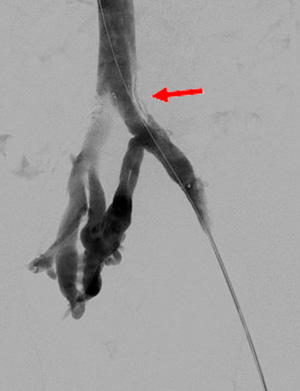

固有肝動脈瘤(赤矢印)に対する開腹血行再建